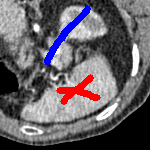

We now introduce two recent methods that incorporate user input to perform selective segmentation. Each involves input in the form of foreground/background regions to indicate relevant structures of interest. An example of this can be seen in Fig. 18, where red regions indicate foreground and blue regions indicate background. We compare against the work of Nguyen et al. Nguyen:12 , which uses a similar convex relaxation framework to the proposed approach, and Dong et al. SRW , which uses a variation of the random walk approach. We summarise the essential aspects of each approach in the following.

In order to further establish the robustness of our method, we now introduce the results of testing our approach against competing interactive segmentation methods on a larger data set. The results are presented in Fig. 17, showing a boxplot of accuracy in terms of TC on a set of 30 CT images (excluding outliers). The target structure we consider is the spleen, as this consists of a relatively homogeneous foreground, appropriate for the approach considered. The data has been manually contoured providing ground truth data for the image set. We compare CAC Nguyen:12 and SRW SRW against our method with five variations of user input for each image. It is worth emphasising here that the input used in the tests is identical for each approach and was not refined in any way. It was designed to mimic what a user, unfamiliar with each approach, might select intuitively. A representative example for three images is shown in Fig. 18. This shows foreground (red) and background (blue) user input regions. For our method, we define the red region as as discussed in §1 and enforce hard constraints on the blue region. We refer to the results of the proposed approach using this input as Ours (i). We also include results of randomising the user input in an identical way to §7.3. For each image we generate 1000 simulated user input choices, which we present as Ours (ii). It is important to note that the difference between Ours (i) and (ii) is only the definition of . The method and parameters are fixed between each.